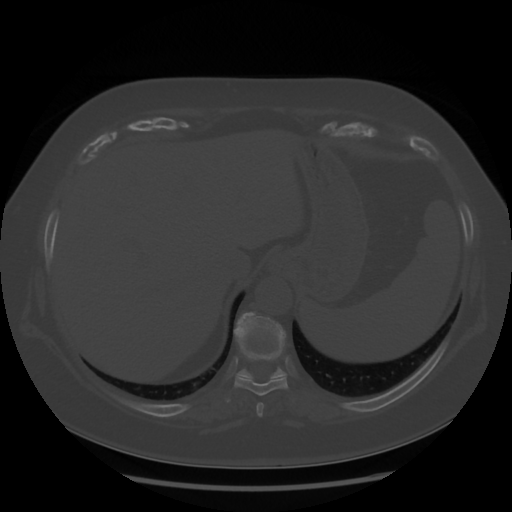

Original NATIVE CT scan (input)

Lung window (WL -600, WW 1500 β†’ Low βˆ’1350, High +150)

Original VENOUS CT scan